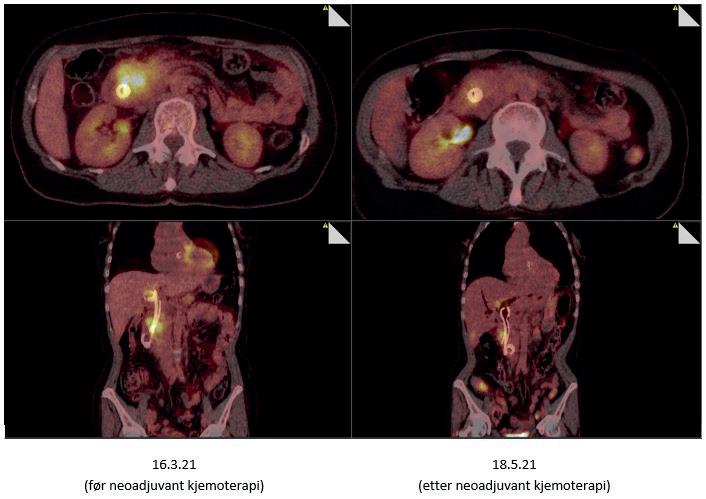

Ved borderline eller lokalavansert sykdom, viste NORPACT-2studien at pasienter som gjennomgikk reseksjon etter preoperativ kjemoterapi, hadde tilsvarende overlevelse som hos pasienter operert direkte. Reseksjonsraten var 47 % for borderline-resektable og 13 % for lokalavanserte svulster, som ellers kun ville fått palliativ behandling om det ikke var for at effektiv kjemoterapi gjorde svulsten resektabel [Farnes, BJS Open, 2023]. Vår praksis er nå – i henhold til den nasjonale NORPACT3-studien [Prosjektbeskrivelse av NORPACT-3 i CRISTIN, besøkt 1.9.2024], som startes i disse dager – å gi pasienter med borderline eller lokalavansert pankreaskreft kjemoterapi i fire måneder før revurdering i MDTmøtet med tanke på reseksjon. Hvis de to første av disse månedene ikke har vist tilstrekkelig behandlingsrespons (vi benytter CT og PET-CT samt tumormarkører CA19-9, CEA og CA125 til preoperativ responsevaluering), skiftes type kjemoterapi midtveis i den preoperative behandlingen. Pasientene behandles i denne fasen enten med mFOLFIRINOX eller gemcitabin+nabpaklitaksel

Ved lokalisert sykdom kan strålebehandling vurderes, spesielt ved langvarig respons etter kjemoterapi. Hvis formålet er tumorkontroll, vurderes konvensjonell strålebehandling med 2 Gy i 25 fraksjoner med konkomitant kapecitabin eller FLV. Vi supplerer diagnostisk CT i responsvurderingen med tumormarkører (CA19-9, CEA, CA125) og FDG PET-CT før behandling og to og fire måneder etter endt

strålebehandling. Ved vedvarende respons bedømt klinisk (symptomer), radiologisk (CT), biokjemisk (tumormarkører) og metabolsk (FDG) er det et rasjonale for å rehenvise til MDTmøtet med tanke på kirurgi, men det skal sies at vi har behandlet få pasienter på denne måten og ennå ikke lyktes med å konvertere inoperabel sykdom til kurativ kirurgi ved hjelp av strålebehandling. I mange tilfeller kan det være mer hensiktsmessig å gi kortere fraksjonering, rettet mot (palliativ) tumorkontroll og symptomlindring.